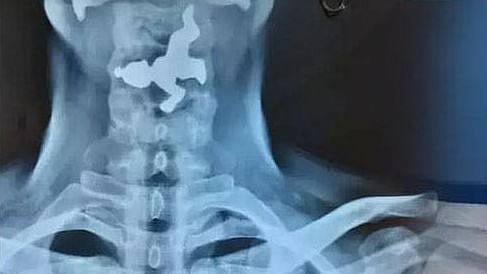

கர்நாடக மாநிலம் பெலகவி மாவட்டத்தில், 45 வயது மிக்க நபர் ஒருவர் தனக்கு தொண்டை வலி இருப்பதோடு மூச்சு விடுவதில் சிரமம் இருப்பதாக கூறி தனியார் மருத்துவமனையை அணுகினார். எனவே அங்குள்ள மருத்துவர்கள் அவருக்கு X-Ray எடுத்து பரிசோதனை செய்தனர். X-Ray ரிப்போர்ட்டை பார்த்த மருத்துவர்கள் அதிர்ச்சியடைந்தனர்.

அதில், அவரது தொண்டையிலுள்ள உணவு குழாயில் இரும்பு வடிவிலான பொருள் ஒன்று சிக்கியுள்ளது தெரிந்தது. பின்னர் இது குறித்து அவரிடம் விசாரித்த போது, தான் எதையும் உட்கோள்ளவில்லை என்று தெரிவித்தார். தொடர்ந்து அவரிடம் கேட்கையில், தான் வழக்கமாக அருகிலிருக்கும் ஒரு கோயிலில் நீராடி, அந்த நீரை பருகுவதாக தெரிவித்தார்.

இதனையடுத்து, அவருக்கு ENDOSCOPY என்ற சிகிச்சை மூலம் தொண்டையில் சிக்கியிருந்த பொருளை தொண்டை வழியே வெளியே எடுத்தனர். இது குறித்து மருத்துவர்கள் கூறுகையில், 45 வயது மதிக்கத்தக்க நபர் ஒருவர் தனக்கு மூச்சு விடுவதில் சிரமமாக இருப்பதாக அணுகினார்.

அவரை பரிசோதனை செய்ததில், தொண்டையில் பொருள் இருப்பது கண்டுபிடிக்கப்பட்டு, சிகிச்சை மூலம் வெளியே எடுக்கப்பட்டது. இந்த சிகிச்சையின்போது உணவுக் குழாயில் சிலையின் இடது கால் சிக்கிக் கொண்டதால் எங்களுக்கு மிகவும் கடினமாகவும் சவாலாக இருந்தது. எனவே எதை சாப்பிட வேண்டுமென்றால் பார்த்து சாப்பிடுங்கள், பருகுங்கள்" என்றனர்.